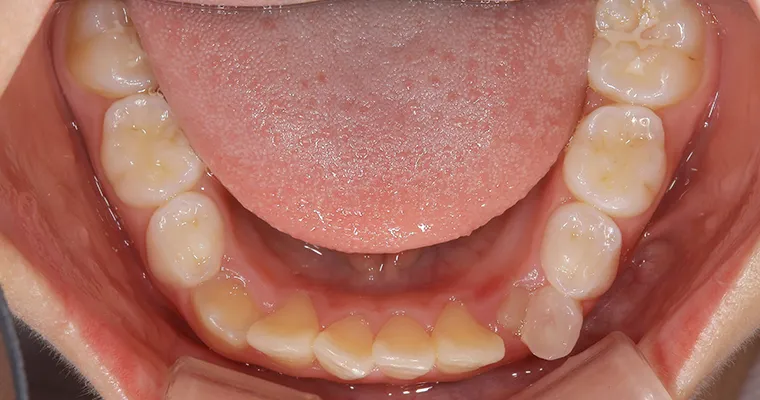

下顎咬合面観

BEFORE

AFTER

| 主訴 | 歯並びが悪い 乳歯と永久歯が重なっている 歯がまっすぐはえてこない |

|---|---|

| 治療期間 | 6-7ヶ月 |

| 治療費 | 440,000円(税込) ※調整、器具、治療後にお渡しするEFLine(矯正後の後戻りを防ぐ器具)も全て込みでの金額となっております。 |

| 治療内容 | 拡大床矯正 EF Lineで筋機能療法 |